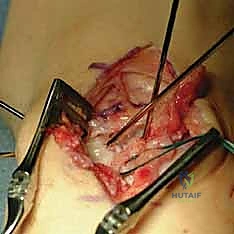

In cases of a tenuous SLIL repair, chronic scapholunate dissociation (beyond 6 weeks) without arthritis, or if the deformity is reducible but requires additional stability, we augment the repair with a dorsal capsulodesis.

- Initial Steps: Perform the SLIL repair exactly as described above, utilizing the same ulnar-based dorsal capsular incision and flap creation.

- Capsular Flap Positioning: After the primary SLIL repair is completed and secured, swing the ulnarly-based capsular flap over the scapholunate interval. Carefully plan the precise location for its attachment to the scaphoid waist. The goal is to secure this flap under tension to further reinforce and stabilize the scapholunate joint.

- Additional Suture Anchors: Place one or two mini suture anchors (1.8 or 2.0 mm) into the scaphoid at the determined location for the flap's distal attachment. Additionally, place another mini suture anchor dorsal-centrally into the lunate.

- Suture Passage and Tensioning: With the capsular flap pulled taut, pass the sutures from the scaphoid suture anchors through the distal aspect of the flap. Then, pass the sutures from the lunate anchor through the central aspect of the flap. Estimate the suture locations carefully to maximize stabilization of the scapholunate joint.

- Final Securing: Once all sutures from both the scaphoid and the lunate are passed through the capsular flap, tie them down securely. This creates a strong dorsal tether, augmenting the primary SLIL repair.

* This image demonstrates the repair augmentation with the ulnar-based capsular (CAPS) flap. Notice the suture anchor knots (arrows) and the placement of the distal suture anchor at the scaphoid, reinforcing the dorsal intercarpal ligament footprint.